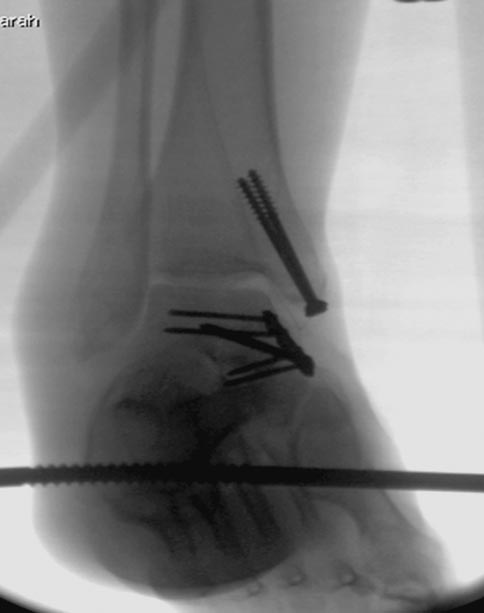

6 день госпитализации-операция на таранной кости.

На 9й день фиксация дистального бедра, где фрагмент Hoffa и вертикальный перелом надколенника, зафиксированы винтами.